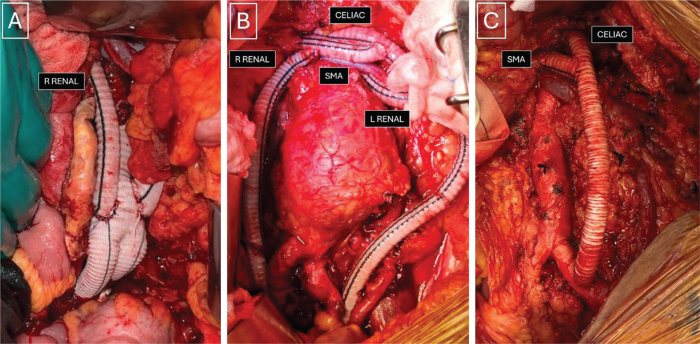

Repair of complex aortic aneurysms such as those involving the thoracoabdominal and pararenal aorta presents a formidable challenge for surgeons with significant perioperative morbidity and mortality. A hybrid procedure combining renovisceral debranching with endovascular aneurysm exclusion has been developed as an alternative approach for high-risk patients. This paper reports our initial experience with hybrid repair for these complex aortic diseases in three high-risk patients.